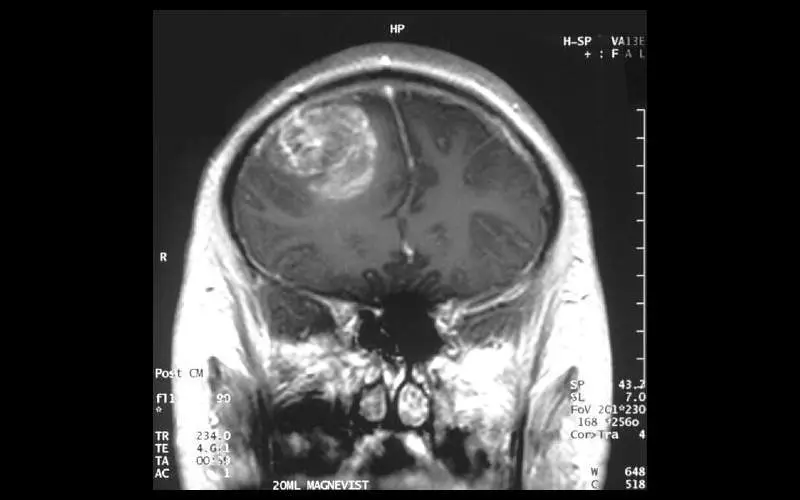

Los ensayos clínicos para un nuevo tratamiento para pacientes con glioblastoma, una forma mortal de cáncer cerebral, han demostrado un rápido éxito, y algunos pacientes experimentaron una disminución dramática en el tamaño del tumor apenas unos días después de su primer ciclo de tratamiento

Apenas unos días después de un único tratamiento, los pacientes experimentaron reducciones dramáticas en sus tumores, y un paciente logró una regresión tumoral casi completa en cinco días después de un tratamiento.

Uno de los pacientes, un hombre de 72 años, experimentó una disminución del 60,7 % en su tumor que se mantuvo durante seis meses, mientras que una mujer de 57 años tuvo una regresión casi completa del tumor solo cinco días después de una única infusión.